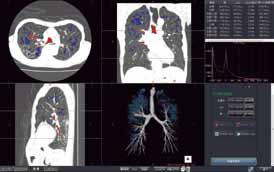

これまでの使用経験を振り返ると「動態を診る検査は全てPhyZiodynamicsの対象といえます。時相情報を基軸にしている領域、例えば心臓では心筋、冠動脈、弁の動態などが詳細に再現できるので、高い利用価値がありますね」と語る。

また、心臓以外の検査での可能性も広いという。その1つが腫瘍の鑑別診断。動きのダイナミック撮影を行ったMRI画像からPhyZiodynamicsを利用して、腫瘍と正常臓器との関係を詳細に評価することで、正常臓器への浸潤の有無が可能になるという。

この他にも、CT/MRIでのperfusion検査にて血液流入のタイミングの違いをより詳細に動的に観察することにより腫瘍の質的診断にも役立つと期待している。「PhyZiodynamicsの動画なら腸全体の蠕動などが自然に再現されます。クローン病であれば、罹患腸管の動きが悪いので、それがより際立って見えます」(片平氏)。